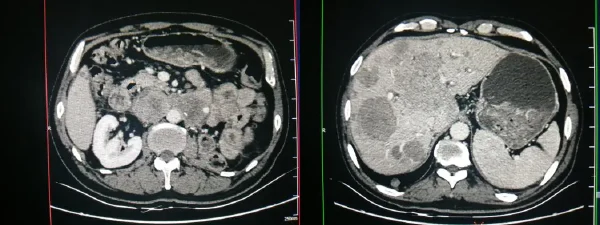

腹膜后肿瘤的诊断是一个复杂且精细的过程,需要结合临床信息、辅助检查结果及医生的实践经验。影像学检查如CT、MRI是目前最主要的诊断手段,能够清晰地展示肿瘤的形态、大小及其与周围组织的关系。

在影像学检查的基础上,医生还可能会进行穿刺活检,通过病理细胞学检查确定肿瘤的性质。这有助于进一步确定治疗方案,比如是否需要进行放化疗,还是可以通过手术完全切除。